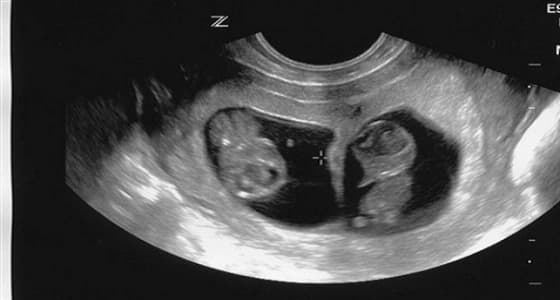

أول علامات الحمل التي يمكن رؤيتها عن طريق الفحوصات هي جريبات الحمل " كيس الحمل " ، والتي تبدو بيضاوية الشكل في تصوير الألتراساوند.

و بعد مرور 4 أسابيع من الحمل يمكن رؤية جريبين " كيسين " إذا كان الحمل بتوأمين غير متطابقين. أما التوأم المتطابق فينمو في جريب واحد، ولا يمكن رصدهما قبل الأسبوع الـ 5 عن طريق الألتراساوند.